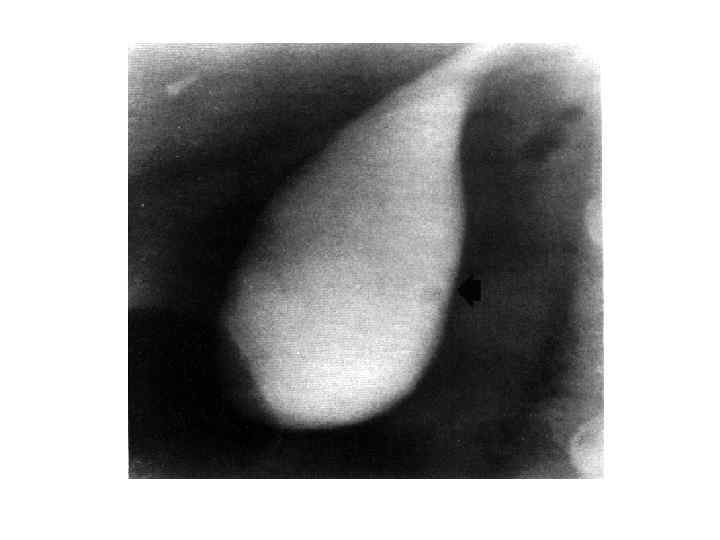

Диагностика • • • Сбор анамнеза Осмотр Обследование передней брюшной стенки Люборатоные данные: общий анализ крови; биохимическое исследование крови, Дуоденальное зоондирование с бактериологическим исследованием всех порций желчи Рентгенологическое исследование УЗИ КТ РХПГ ФЭГДС Лапароскопия радиоизотопное исследование

Диагностика • • • Сбор анамнеза Осмотр Обследование передней брюшной стенки Люборатоные данные: общий анализ крови; биохимическое исследование крови, Дуоденальное зоондирование с бактериологическим исследованием всех порций желчи Рентгенологическое исследование УЗИ КТ РХПГ ФЭГДС Лапароскопия радиоизотопное исследование